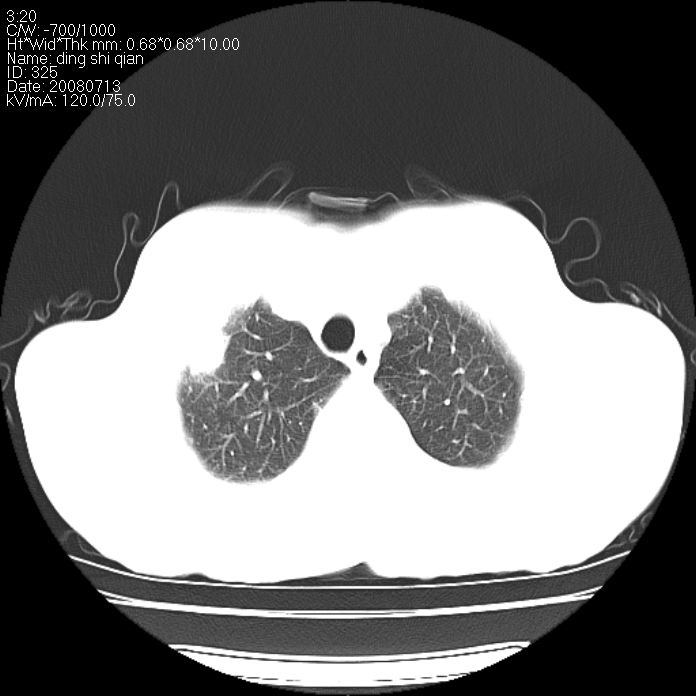

标题: CT14654:男 50岁 近来胸痛 [打印本页]

标题: CT14654:男 50岁 近来胸痛

右侧上肺块状软组织影,浅分叶,边缘毛刺证,与胸膜粘连,考虑:周围性肺癌

右侧上肺块状软组织影,浅分叶,边缘毛刺证,与胸膜粘连,考虑:周围性肺癌!支持!